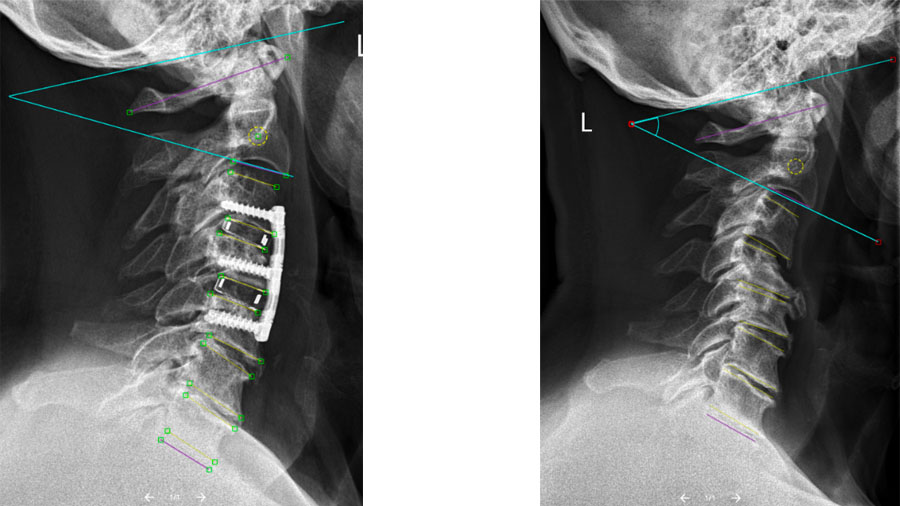

Our recent study, published in the European Spine Journal, explored how multilevel ACDF affects cervical sagittal alignment and the compensatory mechanisms that patients develop to keep their head balanced and their gaze horizontal. (You can read the full study here.)

The study itself was a retrospective radiographic analysis of 290 patients with cervical spondylosis who underwent two- or three-level ACDF, with a minimum of one year of follow-up. Using an image-analysis system, thousands of pre- and postoperative lateral cervical radiographs were assessed to quantify key sagittal alignment parameters. These included:

- Subaxial cervical lordosis (C2–C7)

- Upper cervical lordosis (C0–C2)

- Surgical and unfused segment lordosis

- T1 slope

- Cervical sagittal vertical axis

How does lordosis restoration affect global cervical alignment?

This large dataset—comprising thousands of radiographic images—allowed us to examine how changes achieved at the fused segments related to alignment changes elsewhere in the cervical spine. The analysis showed that improvements in surgical and subaxial lordosis were strongly associated with a reduction of compensatory hyperextension in the upper cervical spine and unfused segments. This supports the concept that multilevel ACDF can induce a system-wide realignment within the spine rather than acting as a purely local intervention in the neck.